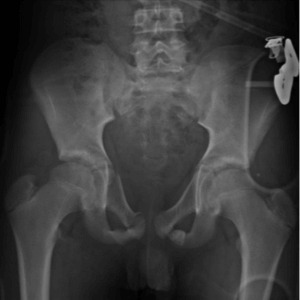

Developmental Dysplasia of the Hip (DDH)

Slipped Capital Femoral Epiphysis (SCFE)